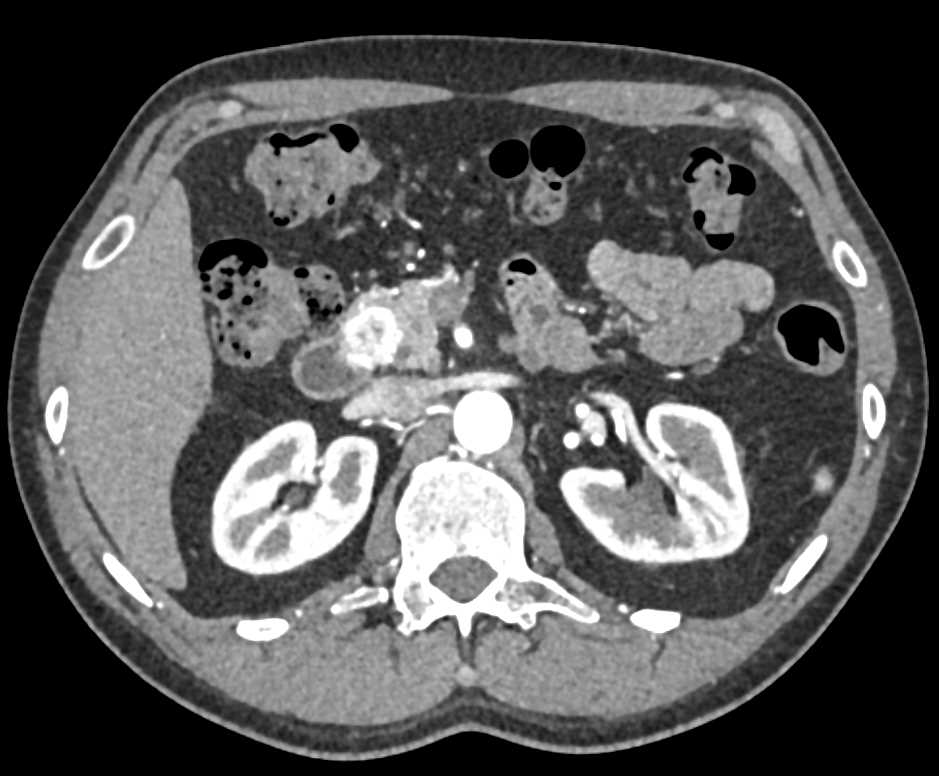

Pancreatic Adenocarcinoma Encases the Celiac and Superior Mesenteric Artery (SMA) and Occludes the Splenic Vein